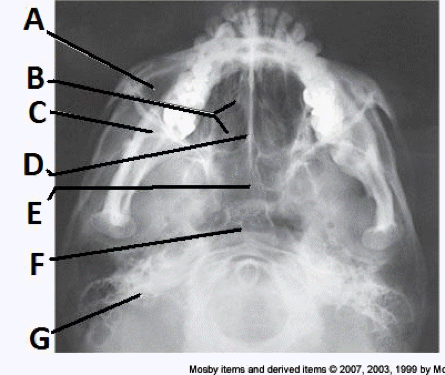

____ 11. Examine the image of the paranasal sinuses below. What projection (method) is demonstrated?

a. PA axial (Caldwell)

b. parietoacanthial (Waters)

c. SMV

d. lateral

b

____ 168. What projection (method) of the facial bones is demonstrated in the image below?

a. AP axial (Towne)

b. PA axial (Caldwell)

c. parietoacanthial (modified Waters)

d. parietoacanthial (Waters)

delete

cc. parietoacanthial (modified Waters)